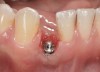

Case Scenario No. 5

Problem: The implant is placed too facial and shallow in depth. The restoration is in the esthetic zone or is cosmetically unacceptable to the patient. Unlike clinical scenario No. 1, there will not be adequate soft-tissue volume after decoronation and/or augmentation to reposition the restoration from a prosthetic standpoint.

Solution: Using a reverse-torque device on high, remove the implant with minimal trauma to the surrounding periodontium. Let the area heal like an extraction socket and place a new implant in the proper position 8 to 10 weeks later. Restore the implant, which will now be in a better restorative and esthetic position, with either a screw- or cement-retained crown.

The rationale for not grafting at the time of implant removal is biologic. Frequently, there is a minimal zone of keratinized attached gingiva around a poorly positioned implant. Allowing the soft tissues to heal and mature in situ (ie, nature’s connective tissue graft) will eliminate the need to coronally reposition the flap, thereby leaving the mucogingival junction in its original position.

The following case report provides an example of this case scenario: A 24-year-old white male presented with congenitally missing tooth No. 26 restored with a single-tooth cement-retained implant restoration. The implant was placed excessively to the facial aspect of the edentulous site and too shallow, and the periodontal phenotype was thin scalloped (Figure 32). In an effort to mimic the lost midfacial soft tissues, pink ceramics were used as a cosmetic facade. Even though the restoration was not in the esthetic zone, the patient was highly displeased with the esthetic outcome and sought remediation.

Fig 32. A dissatisfied patient presented with significant midfacial recession of implant restoration of tooth No. 26. Pink ceramic material was used unsuccessfully to prosthodontically compensate for the lost midfacial tissue.

Figure 32

Fig 33. Excessive facial angulation of the implant placement shown with an abutment driver in the access screw hole.

Figure 33

Fig 34. A surgical cover screw was placed in an attempt to decoronate the implant and gain soft-tissue coverage in situ.

Figure 34